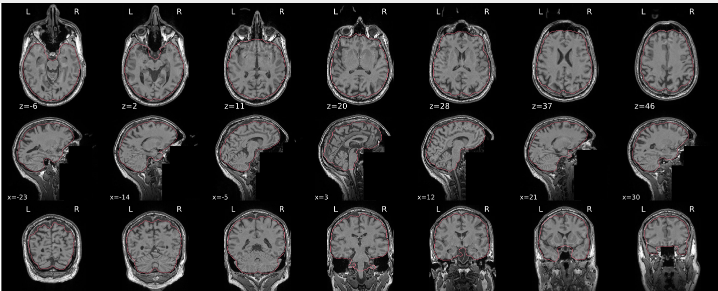

T1w skull stripping

Skull stripping is the process separating the brain (cortex and cerebellum) from the skull. The red line follows the outline of the brain and it separates it from the skull.

Example of a good subject

- There are no skull stripping errors, such as portions of the brain missing, or too much of the skull retained

- The red line follows the outline of the brain

Example of a bad subject

- There are skull stripping errors, such as portions of the brain missing, or too much of the skull retained

- NOTE: check all the images (slices) in the report. If only one image (slice) looks problematic, it is possible that the subject is okay and it is just a visual issue in that particular screenshot

Summary

| Good | Bad |

|---|---|

| The brain is fully inside the red line | Structures like the cranium or the eyes are inside the red line |

| No important brain structures are outside of the red line red line follows the natural outline of the brain | Important brain structures are missing inside of the red line |

-> if only one slice is problematic, it could be an issue related to the visual depiction of the data instead of an issue related to the test subject